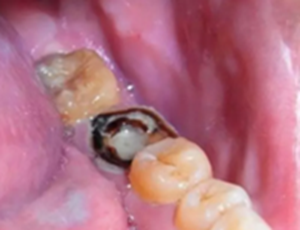

蛀牙:牙齒齲壞到牙齦以上或者牙齦以下1-2mm,牙根長(zhǎng)度仍足夠長(zhǎng)的話,可以保留牙根,經(jīng)過(guò)根管治療可打樁做冠修復(fù)。

每顆牙齒都是有用的,醫(yī)生也是會(huì)盡量保留牙根,保留牙根的最大的意義在于可以降低鑲牙的痛苦,并且能減輕經(jīng)濟(jì)負(fù)擔(dān)。如果醫(yī)生說(shuō)能搶救試試的話,一定乖乖聽醫(yī)生的!

嚴(yán)重蛀牙:牙冠遭到嚴(yán)重破壞的,而且牙根或牙周情況無(wú)法做樁冠修復(fù)的。